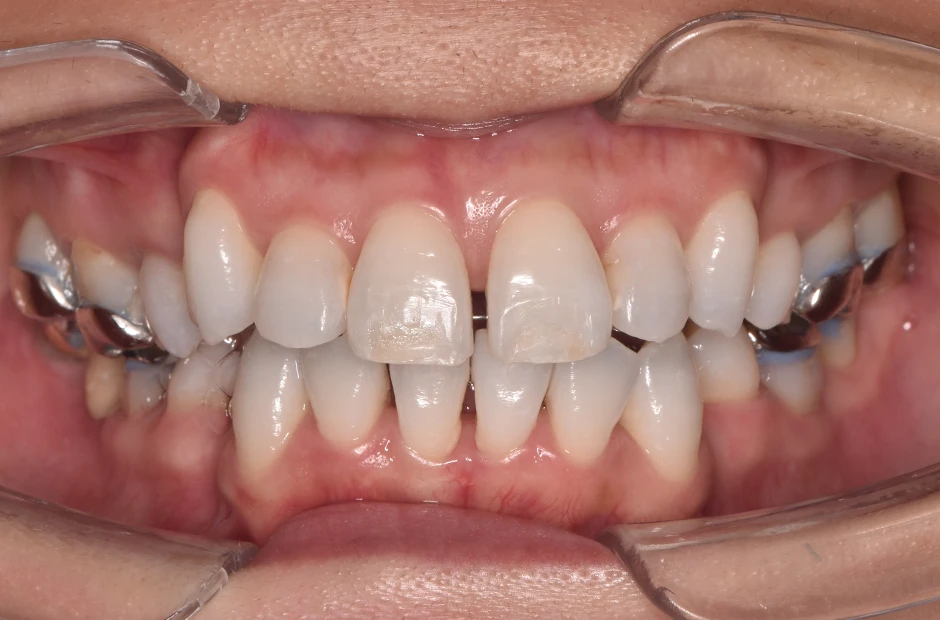

過蓋咬合

| 診断名・主訴 | 過蓋咬合 |

|---|---|

| 年齢・性別 | 29歳・女性 |

| 治療期間・回数 | 2年 |

| 治療に用いた主な装置 | ブラケット矯正 |

| 抜歯部位 | なし |

| 治療費 | 60万円(税抜) |

| リスク・副作用 | 装置による違和感・疼痛・歯肉退縮・歯根吸収・虫歯のリスクなど |

治療前

治療中

治療後